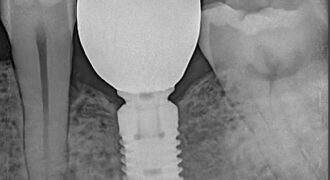

Best Dental Implant Clinic in Dhaka

Take Another Chance to Smile and Visit best dental implant clinic in Dhaka Looking for best dental implant clinic in Dhaka? At the best dental clinic with Dr Rahman in Dhaka located in Banani, are providing advanced dental implant solution to restore missing teeth, smile, aesthetics and function with long term stability. Whether you missing … Continue reading Best Dental Implant Clinic in Dhaka